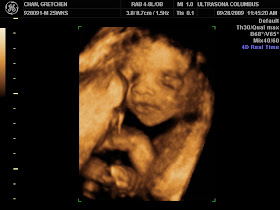

Showing Off My 25 Week 3d Ultrasound Pics October 2016 Babies